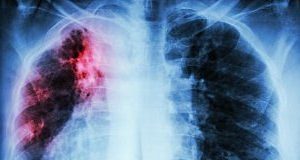

Home Tags Tuberculosis rates

Tag: tuberculosis rates